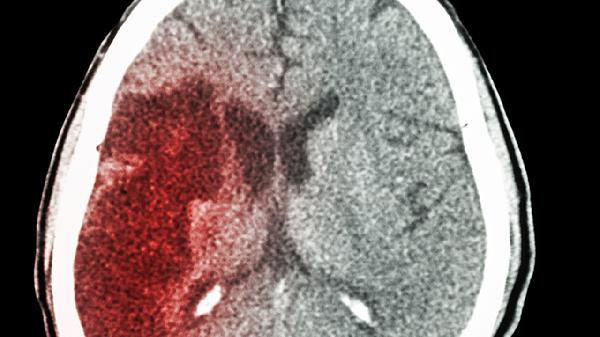

研究462位中风患者,发现:易患中风的人,大多都有这3个共性

中风这个"沉默杀手"来得总是猝不及防,但真的毫无征兆吗?最新研究追踪了462位中风患者的生活轨迹,发现他们身上竟然藏着惊人的相似点。这些藏在日常生活中的危险信号,可能正在悄悄为你的血管埋下"定时炸.弹"。